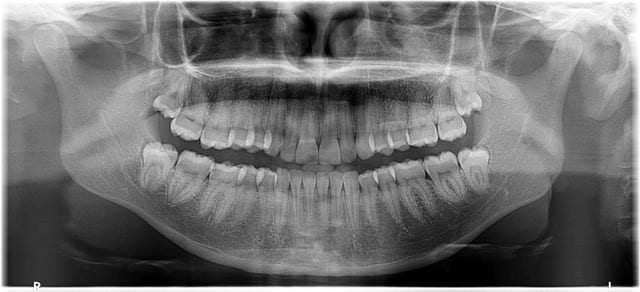

Je proposerai l'avulsion des 4 dents de sagesse en 1 séance en milieu spécialisé

D'évidence y pas de place ,ça va récidiver et le reste est impeccable !

Attention petites caries : 46 distale 47 mesiale et peut être bien en distal de 47 et 37 un petit début ....

Certe ya pas la place... mais c'est une PREMIERE péricoronarite...

L'indication est posée, si on attends risque de douleurs, et de carie interdentaire.

tout à fait d'accord, même sans photo et en étant conscient qu'une pano déforme beaucoup à ce niveau, on voit quand même le début d'un kyste marginal postérieur.